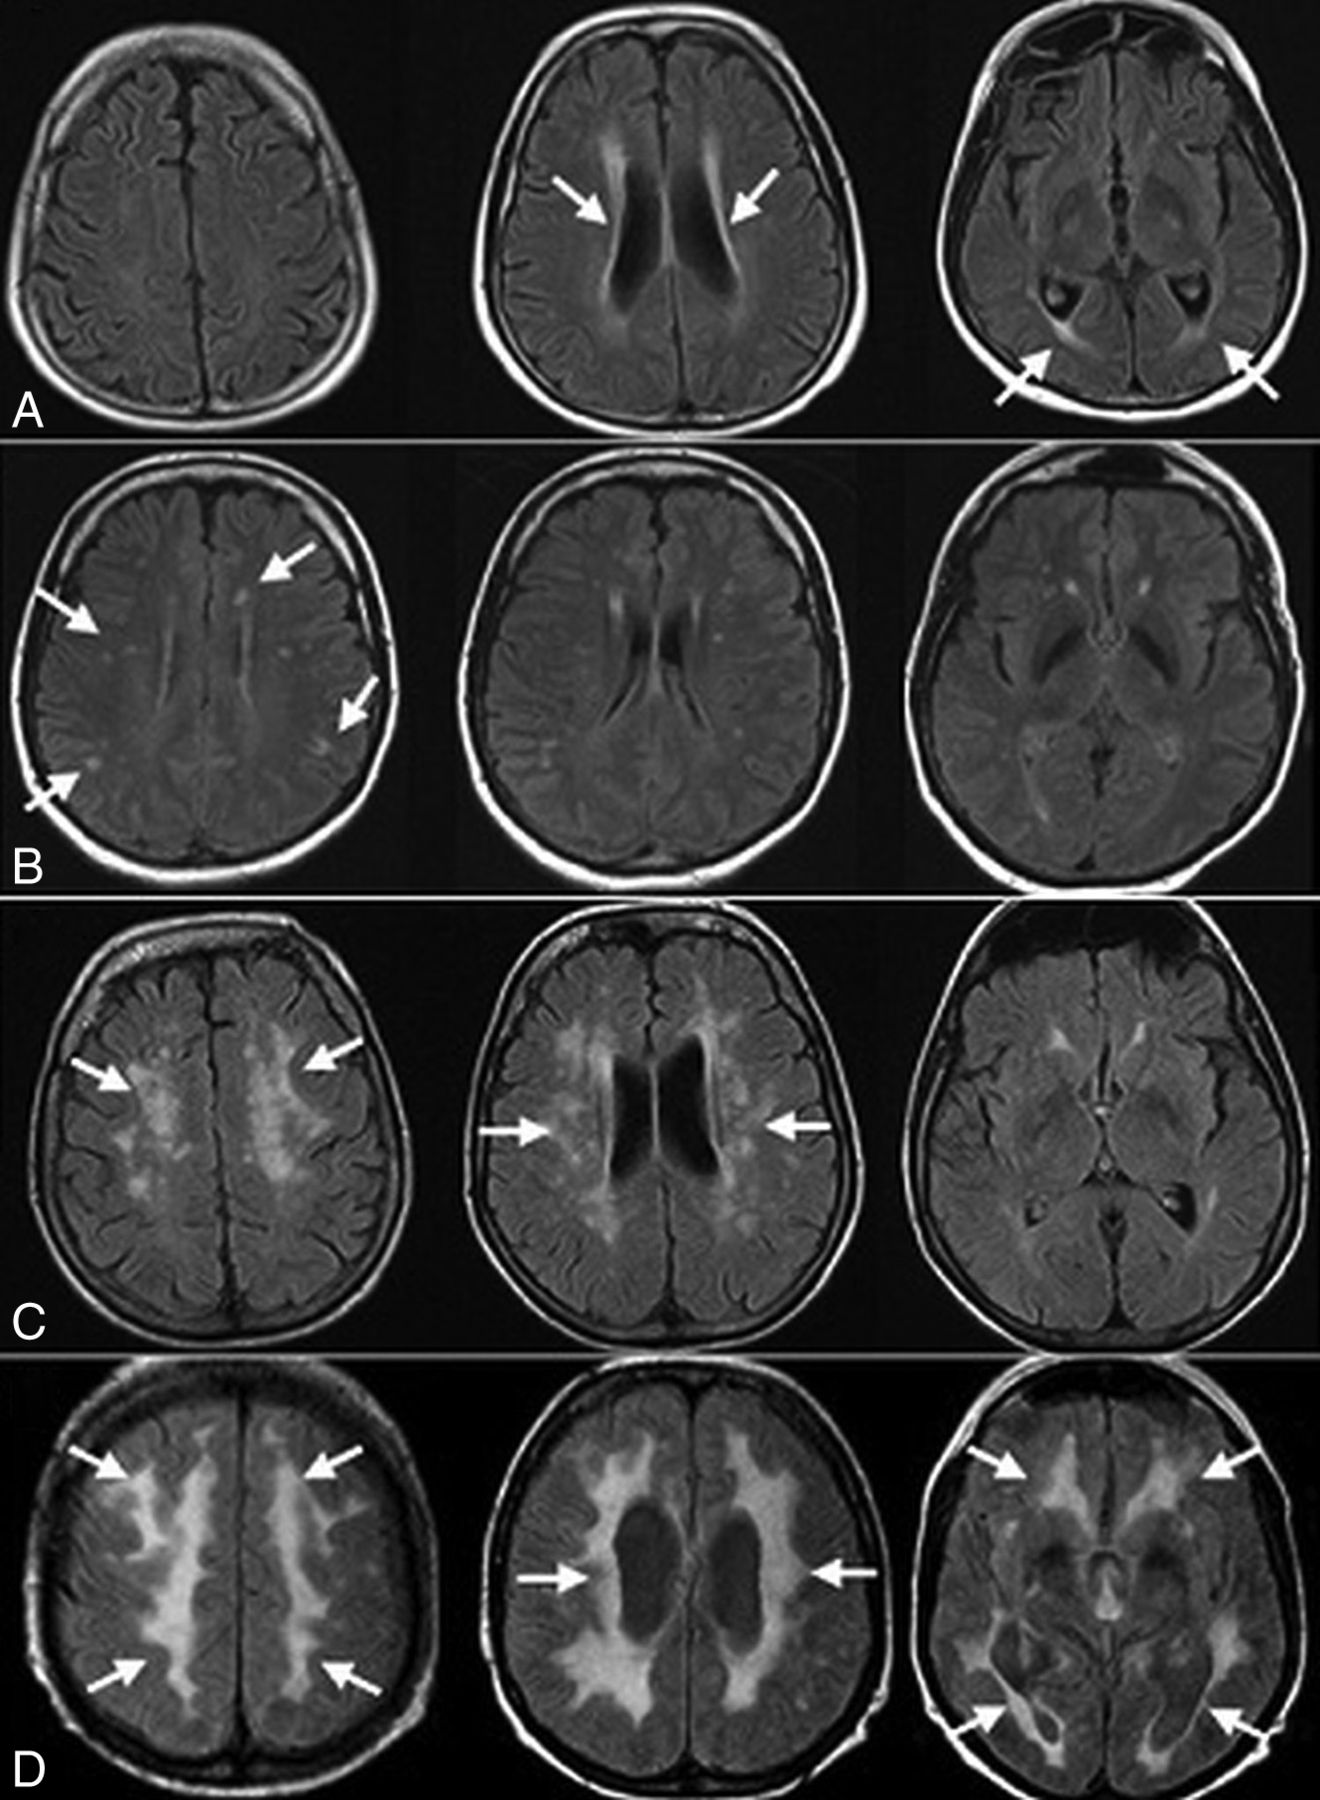

White matter abnormalities on T2-weighted and FLAIR images were seen in 18 patients (69.2%). These changes varied in terms of distribution and extension (Fig 3). Extension of WM changes was characterized by a periventricular and frontoparietal predominance (Fig 4A, -B). Involvement of other subcortical (basal ganglia, thalamus) and infratentorial structures was seen in 3 patients (11.5%) (Fig 4C, -D). Older age was associated with more severe white matter lesions (r = 0.71, P < .001). All white matter lesions were nonenhancing and spared the U-fibers.

Axial FLAIR MR images show varying degrees of white matter lesions. Patients 1 and 26 (A and B) show a mild degree of white matter lesions, with faint periventricular (A; arrows) and small scattered signal intensities (B; arrows). In patient 4 (C), images show patchy signal intensities (arrows), representing a moderate degree of white matter lesions. A more diffuse, vanishing high signal intensity (arrows) is seen in images (D) for patient 7.